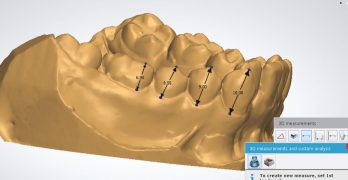

Evaluación del posicionamiento de los brackets: un sistema personalizado frente al método convencional

El artículo con el que empezamos esta semana se llama Evaluation of Bracket Positioning; A Customized System Versus the … [Leer más...] acerca de Evaluación del posicionamiento de los brackets: un sistema personalizado frente al método convencional